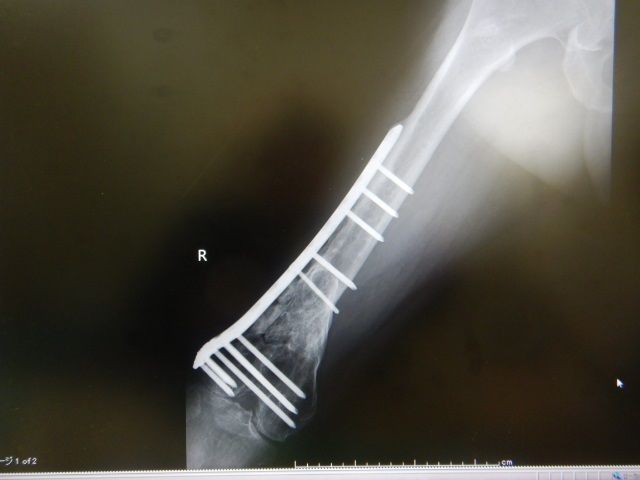

±¦ÂȾǯÄê´üÅÀ¸¡

¼õ½ý¤«¤éº£Ç¯¤Ç13ǯÌܤȤʤꡢȾǯËè¤ÎÄê´ü¸¡ºº¤Ë¹Ô¤Ã¤Æ¤¤Þ¤·¤¿¡£

ÆÃ¤Ë²Ä¤â̵¤¯ÉԲĤâ̵¤¯

ÊѲ½¤âº¹¤Û¤É¸«¤é¤ì¤Ê¤¤¾õÂ֤Ǥ¹¡£

°ì±þÈô¹Ôµ¡¤Ë¾è¤ë¤«¤âÃΤì¤Ê¤¤¤È»×¤¤

ÆüËܸì¤È¸øÍѸì¤Î±Ñ¸ì¤Ç¿ÇÃǽñ¤ò

½ñ¤¤¤ÆÌ㤤¤Þ¤·¤¿¤¬

º£¤Î½ê³¤³°½ÐÄ¥¤Ï̵¤¤¤«¤âÃΤì¤Ê¤¤¡£

¥í¥Ã¥¥ó¥°¥×¥ì¡¼¥È¤ò³°¤·¤¿¤¤¤±¤É

¤Þ¤À¡¢¤Þ¤¿ÀÞ¤ì¤ë¥ê¥¹¥¯¤¬¤¢¤ë¤Î¤Ç

¤³¤Î¥Á¥¿¥ó¥×¥ì¡¼¥È¤Ï¡¢¾Æ¾ì¤Þ¤Ç»ý¤Ã¤Æ¤æ¤¯»ö¤Ë¤Ê¤ê¤½¤¦¡£